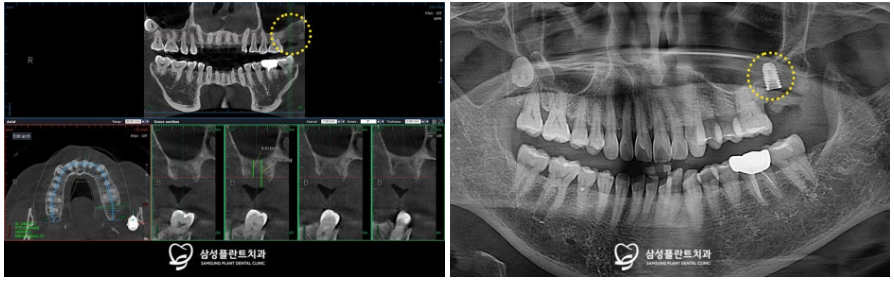

더욱 정밀한 체크를 위해

3D-CT 촬영을 통한 정밀 분석도 시행하였고,

사랑니 발치와 함께

환자분께서 불편을 느끼고 있는 치아는

발치 후 임플란트 식립을

진행하기로 계획했습니다.

그리고 향후 임플란트를

식립해야 할 부위의

뼈 양이 부족한 상태라

발치 후 뼈이식을 먼저 진행하기로 했답니다.

3D-CT 정밀 분석을 통해

식립할 임플란트의 위치 및 방향등을

꼼꼼하게 체크한 후

수술을 진행했습니다.

발치 및 뼈이식을 진행하고

4개월의 충분한 회복 기간을 거친 뒤

임플란트 수술을 진행한 모습입니다.